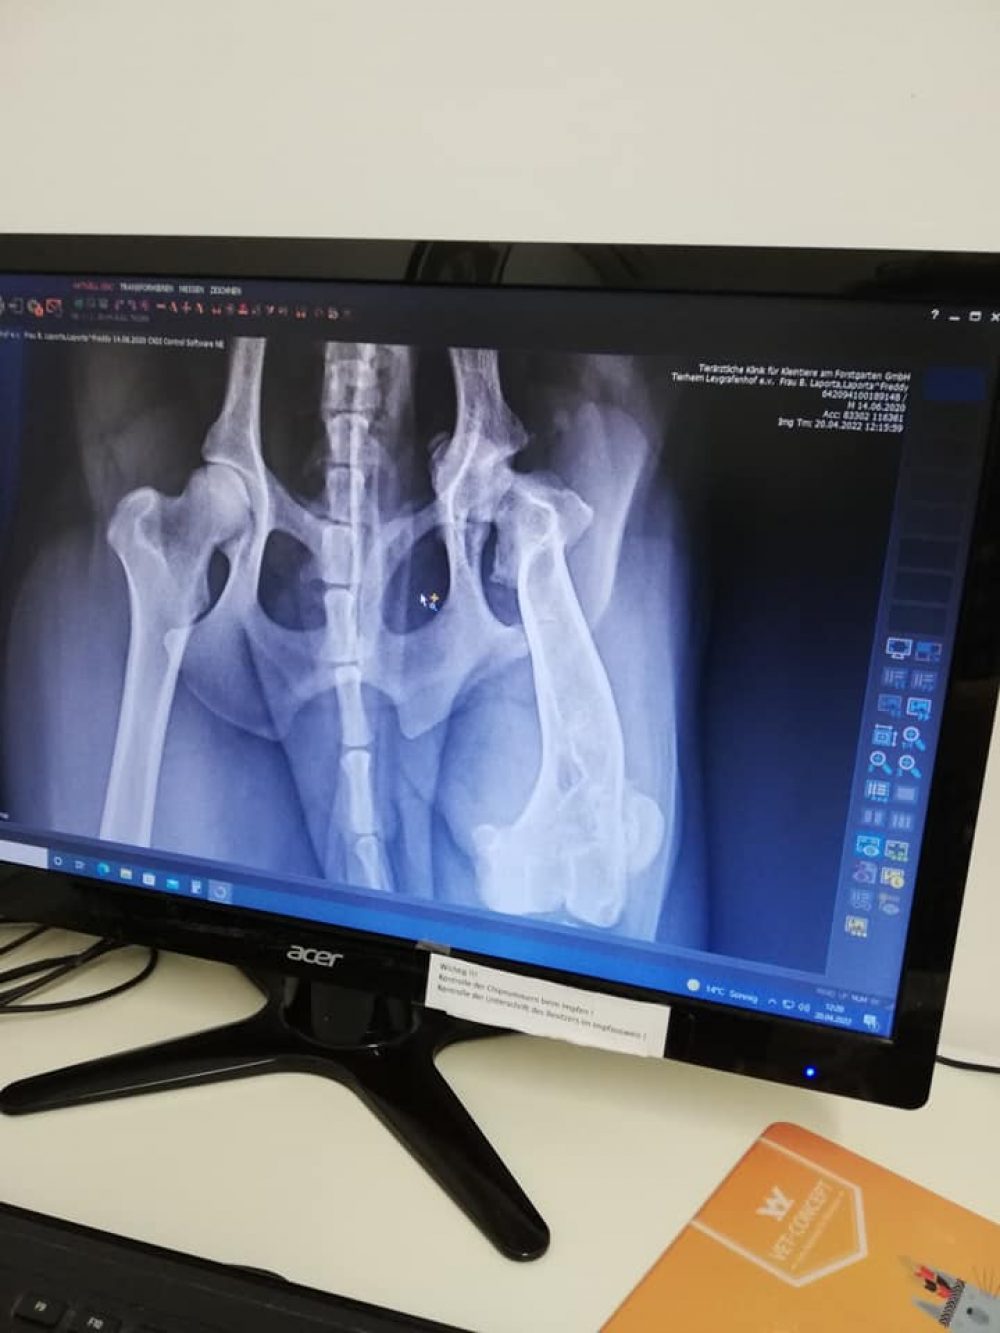

Er wurde bereits auf Herzwurm, Ehrlichiose, Borreliose und Leishmaniose getestet und alles war negativ. Doch leider wurde beim Tierarzt Check festgestellt, dass am linken Bein der Hüftknopf raus ist und dass das Knie falsch zusammen gewachsen ist. Diese Schäden scheinen schon länger vorzuliegen.